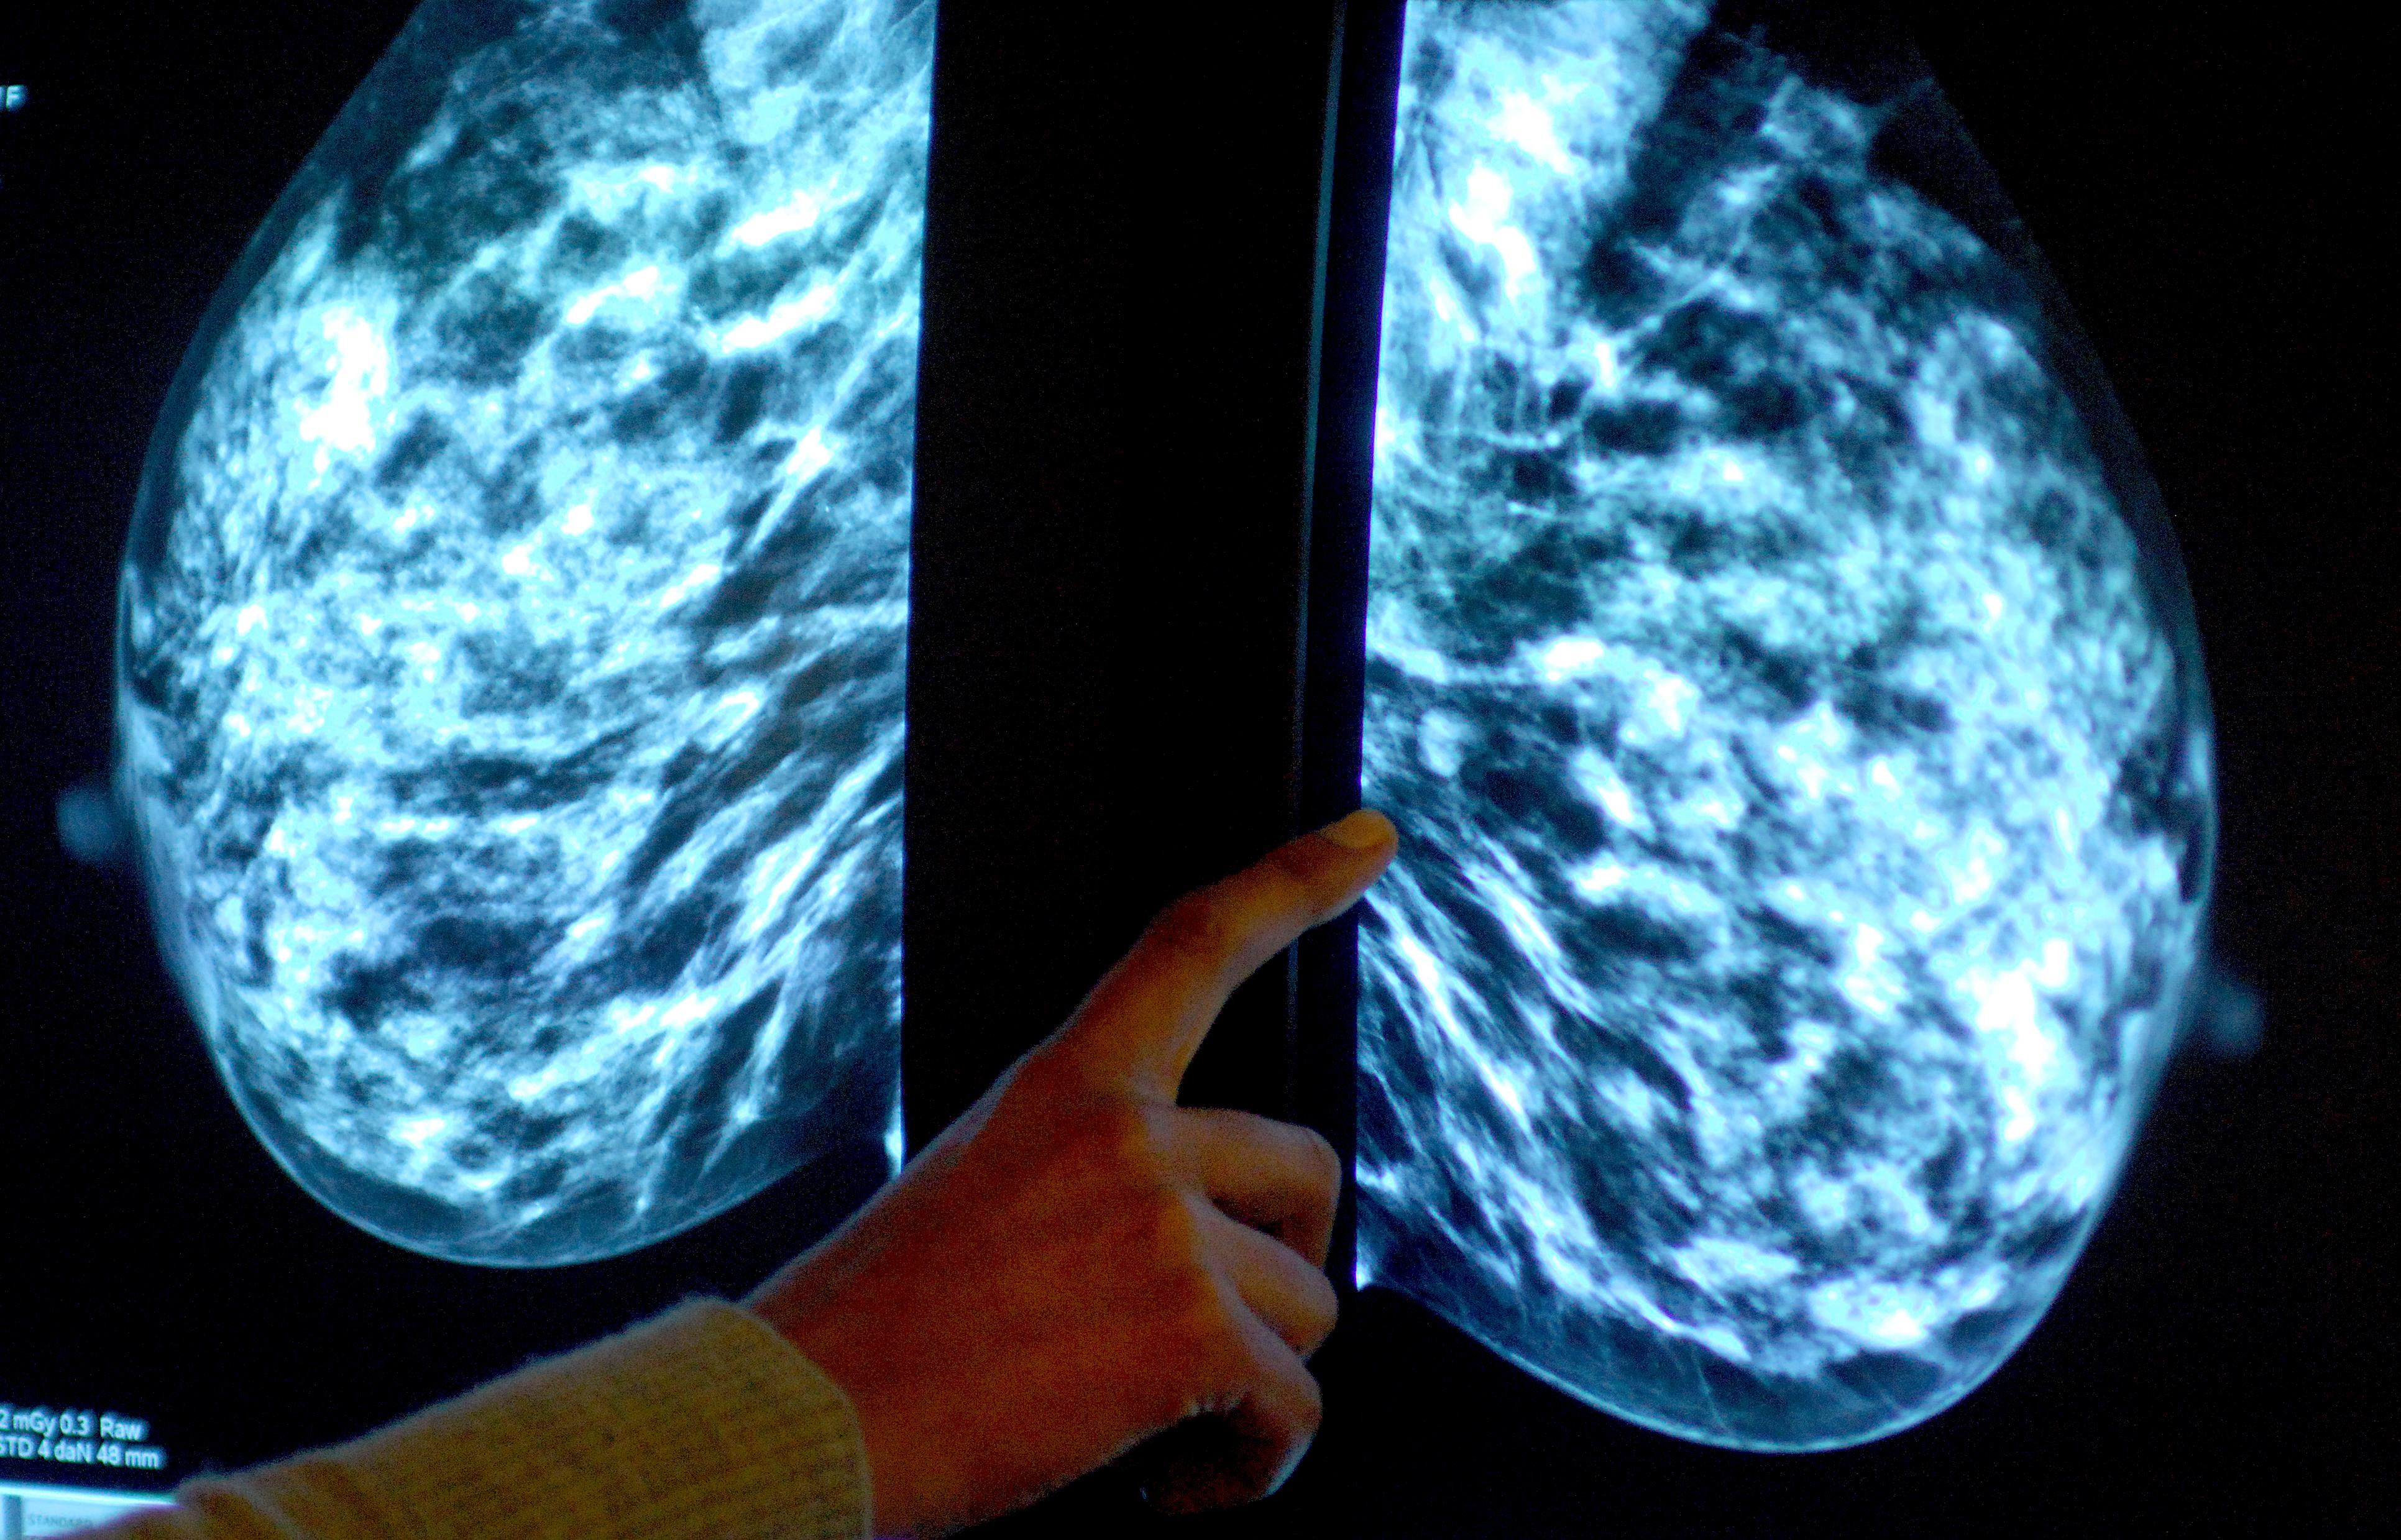

More women in Devon undergo breast cancer screening – as NHS England target met for first in five years

Breast screening uptake in Devon remains below pre-pandemic levels